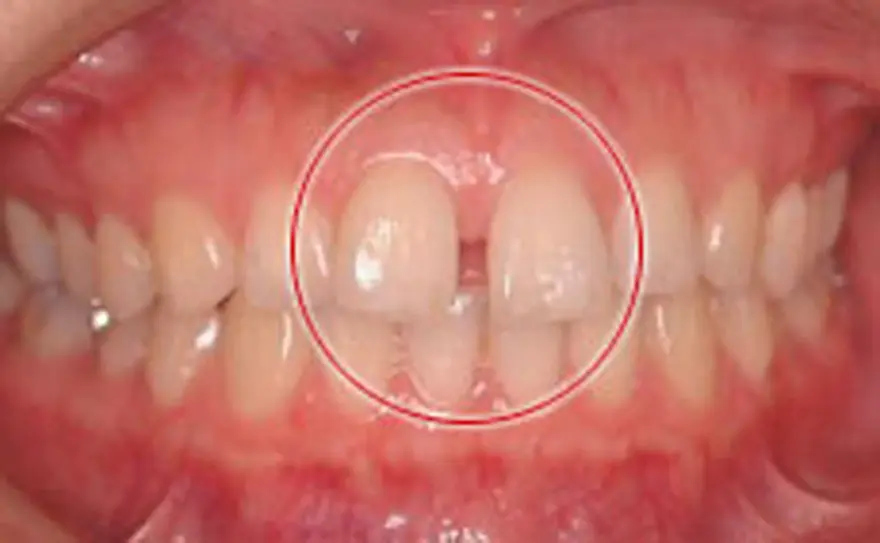

MTM(部分的な矯正)治療例2

矮小歯にセラミックを被せたケース

| 患者さまの年齢・性別 | 30代・女性 |

| 治療期間 | 5ヵ月 |

| 治療費(税込) | 242,000円 |

| 主訴 | 前歯の隙間が気になる。 |

| 診断名・主な症状 | 正中離開 左上の前歯の横の歯が矮小歯という本来より小さい歯です。 |

| 治療に用いた主な装置 | セルフライゲーションブラケット装置(デイモンシステム) |

| 治療内容 | 中央の隙間を閉じた後、そのままでは再度隙間があいてしまうおそれがあります。そのため、矮小歯の表面をわずかに削り、セラミックのシェルを表面につけて歯の幅を広くしています。 |

| 抜歯部位 | 非抜歯 |

| 通院回数・メンテナンス頻度 | 5回 |